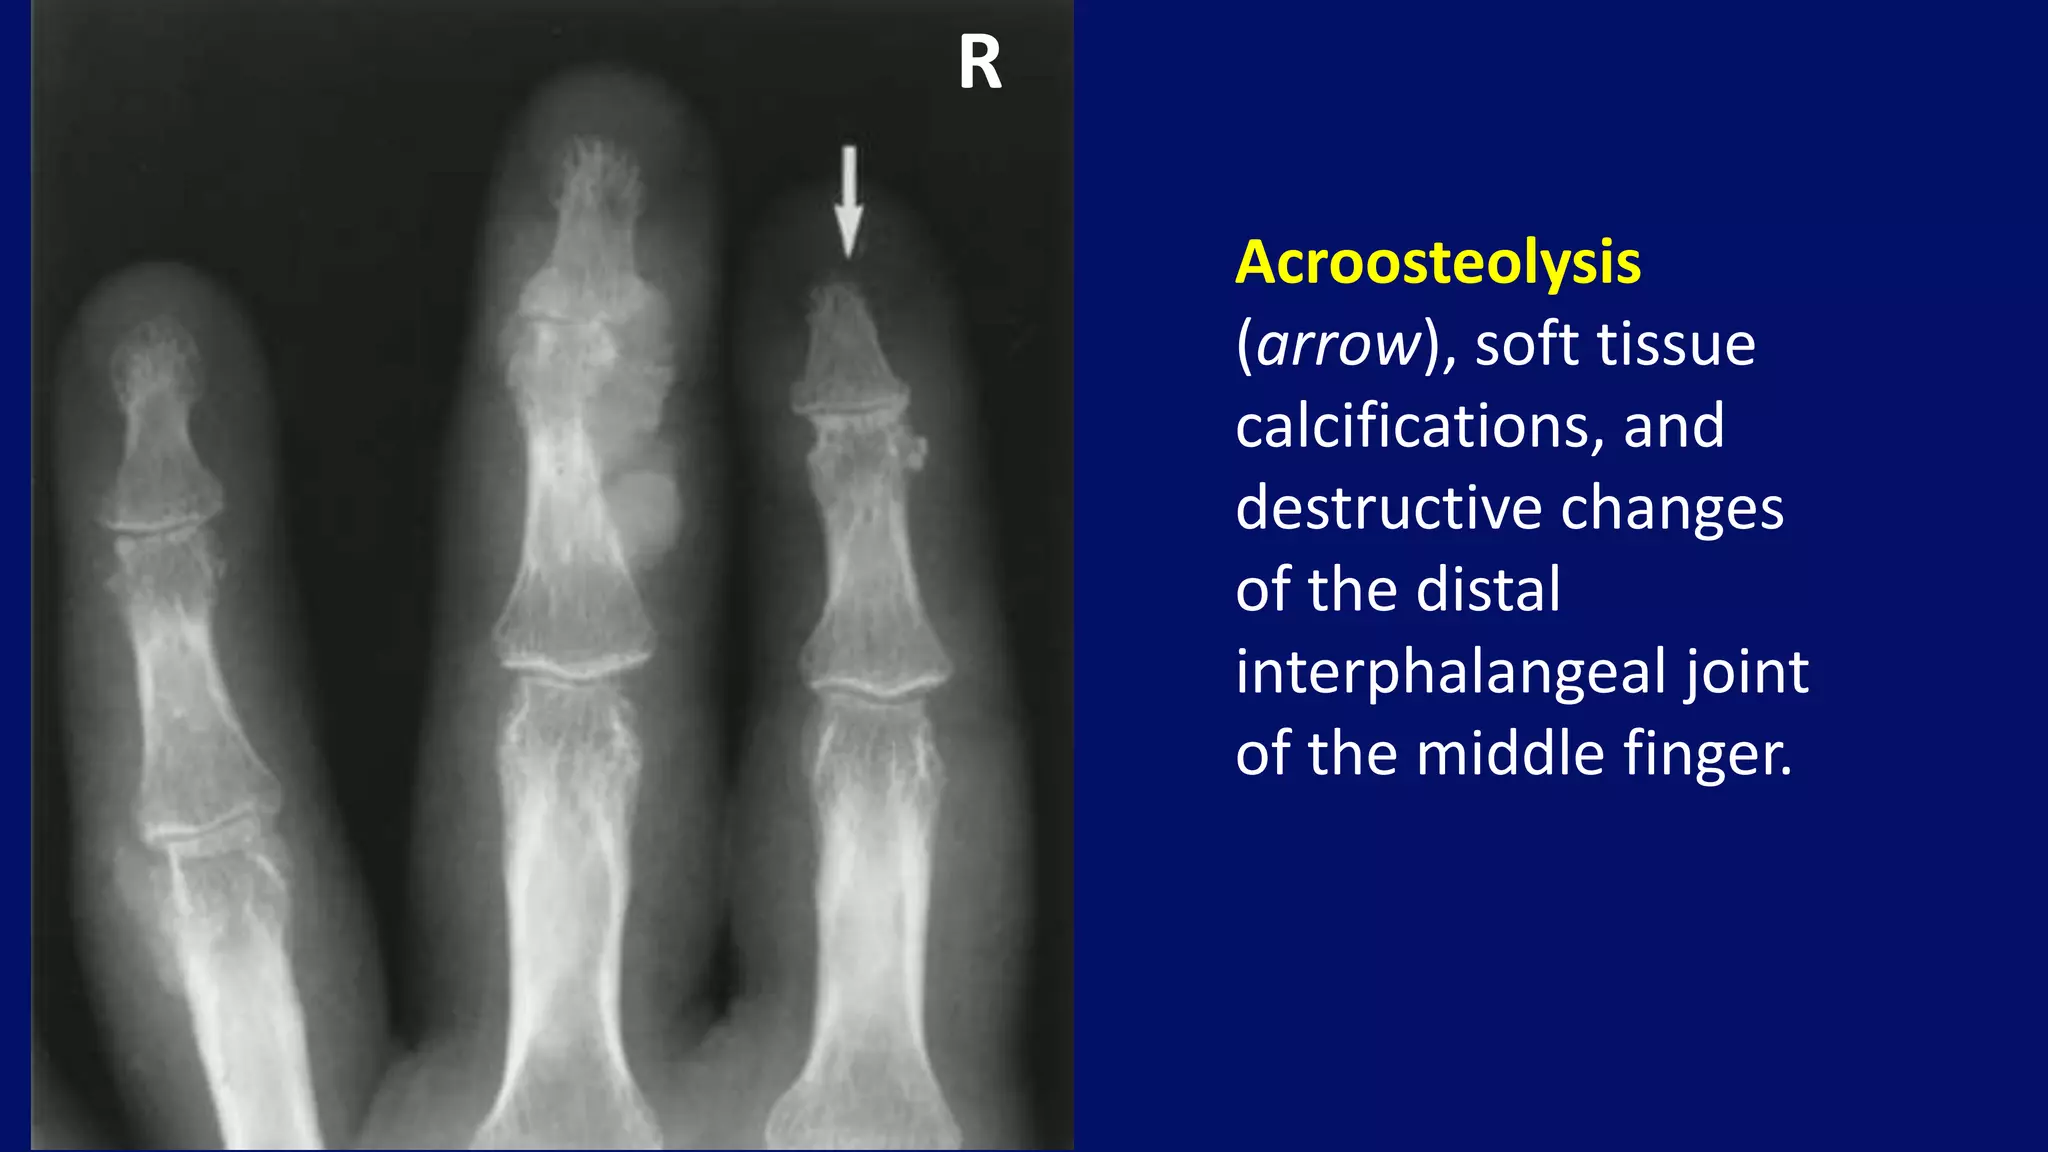

Acroosteolysis

(arrow), soft tissue

calcifications, and

destructive changes

of the distal

interphalangeal joint

of the middle finger.

R

• #80 A dorsovolar radiograph of the fingers of a 44-year-old woman reveals acroosteolysis (arrow), soft tissue calcifications, and destructive changes of the distal interphalangeal joint of the middle finger.